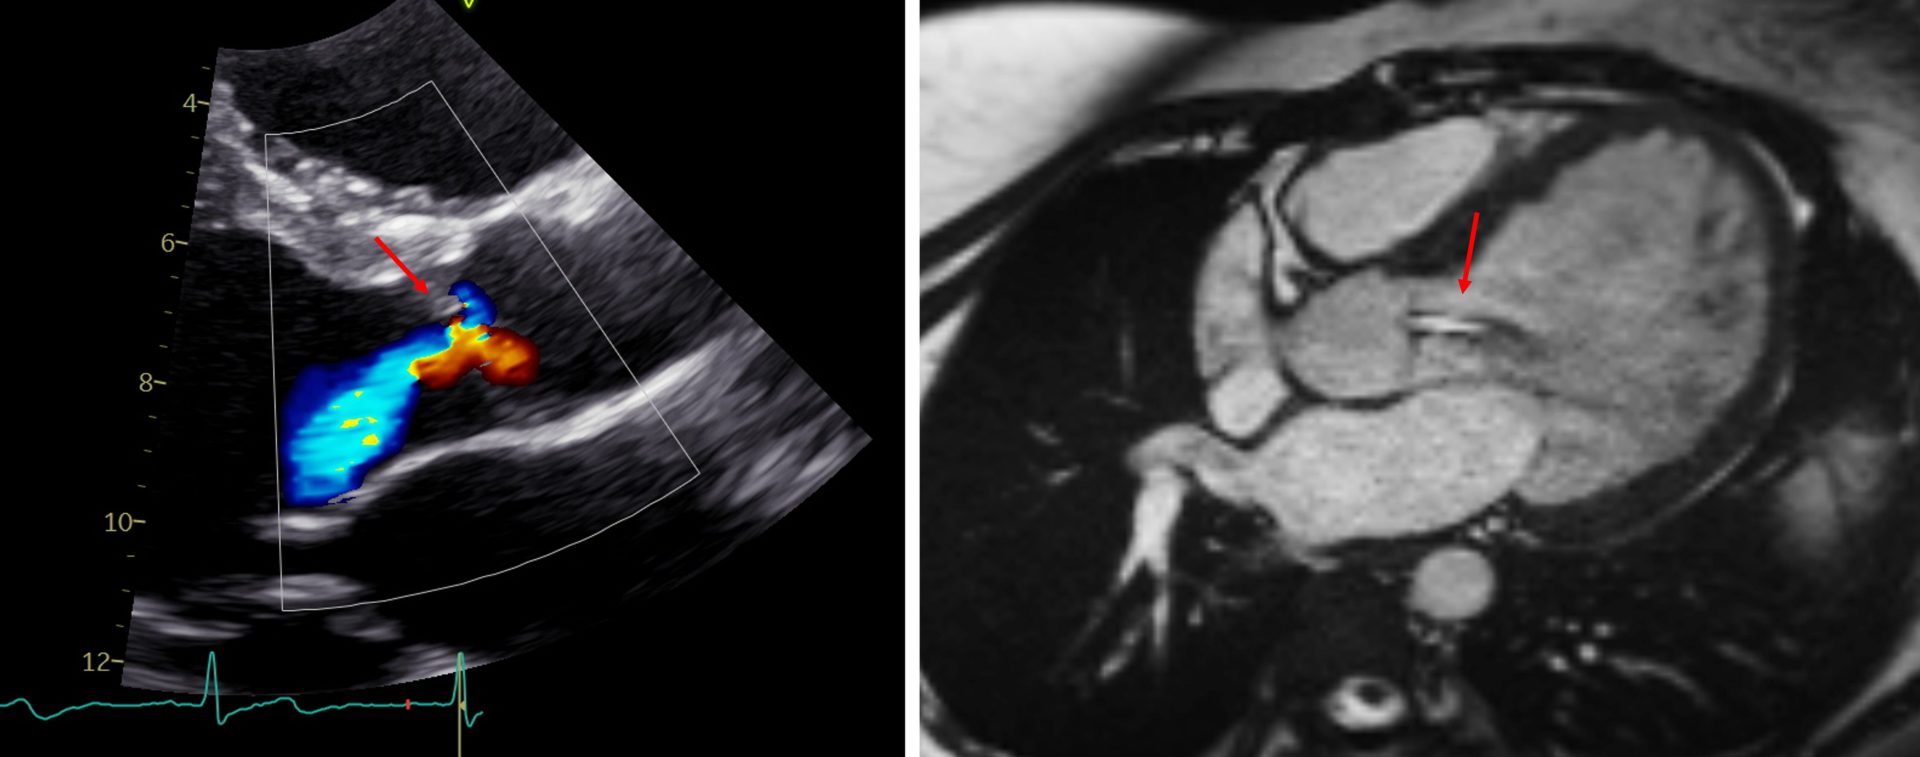

- Echokardiographie- (links) und MRT-Aufnahme (rechts) bei höhergradiger Aortenklappeninsuffizienz (Pfeil).

Im Rahmen dieser Studie möchten wir nun durch Auswertung von Herzultraschallbildern und Herz-MRT-Bildern aus zahlreichen deutschen Kinderherzzentren Kriterien erheben, die die Entscheidung zur Operation erleichtern sollen. Diese Kriterien sollen helfen, eine langfristig ungünstige Schädigung der linken Herzkammer bei jungen Patienten mit Aortenklappeninsuffizienz zu verhindern.